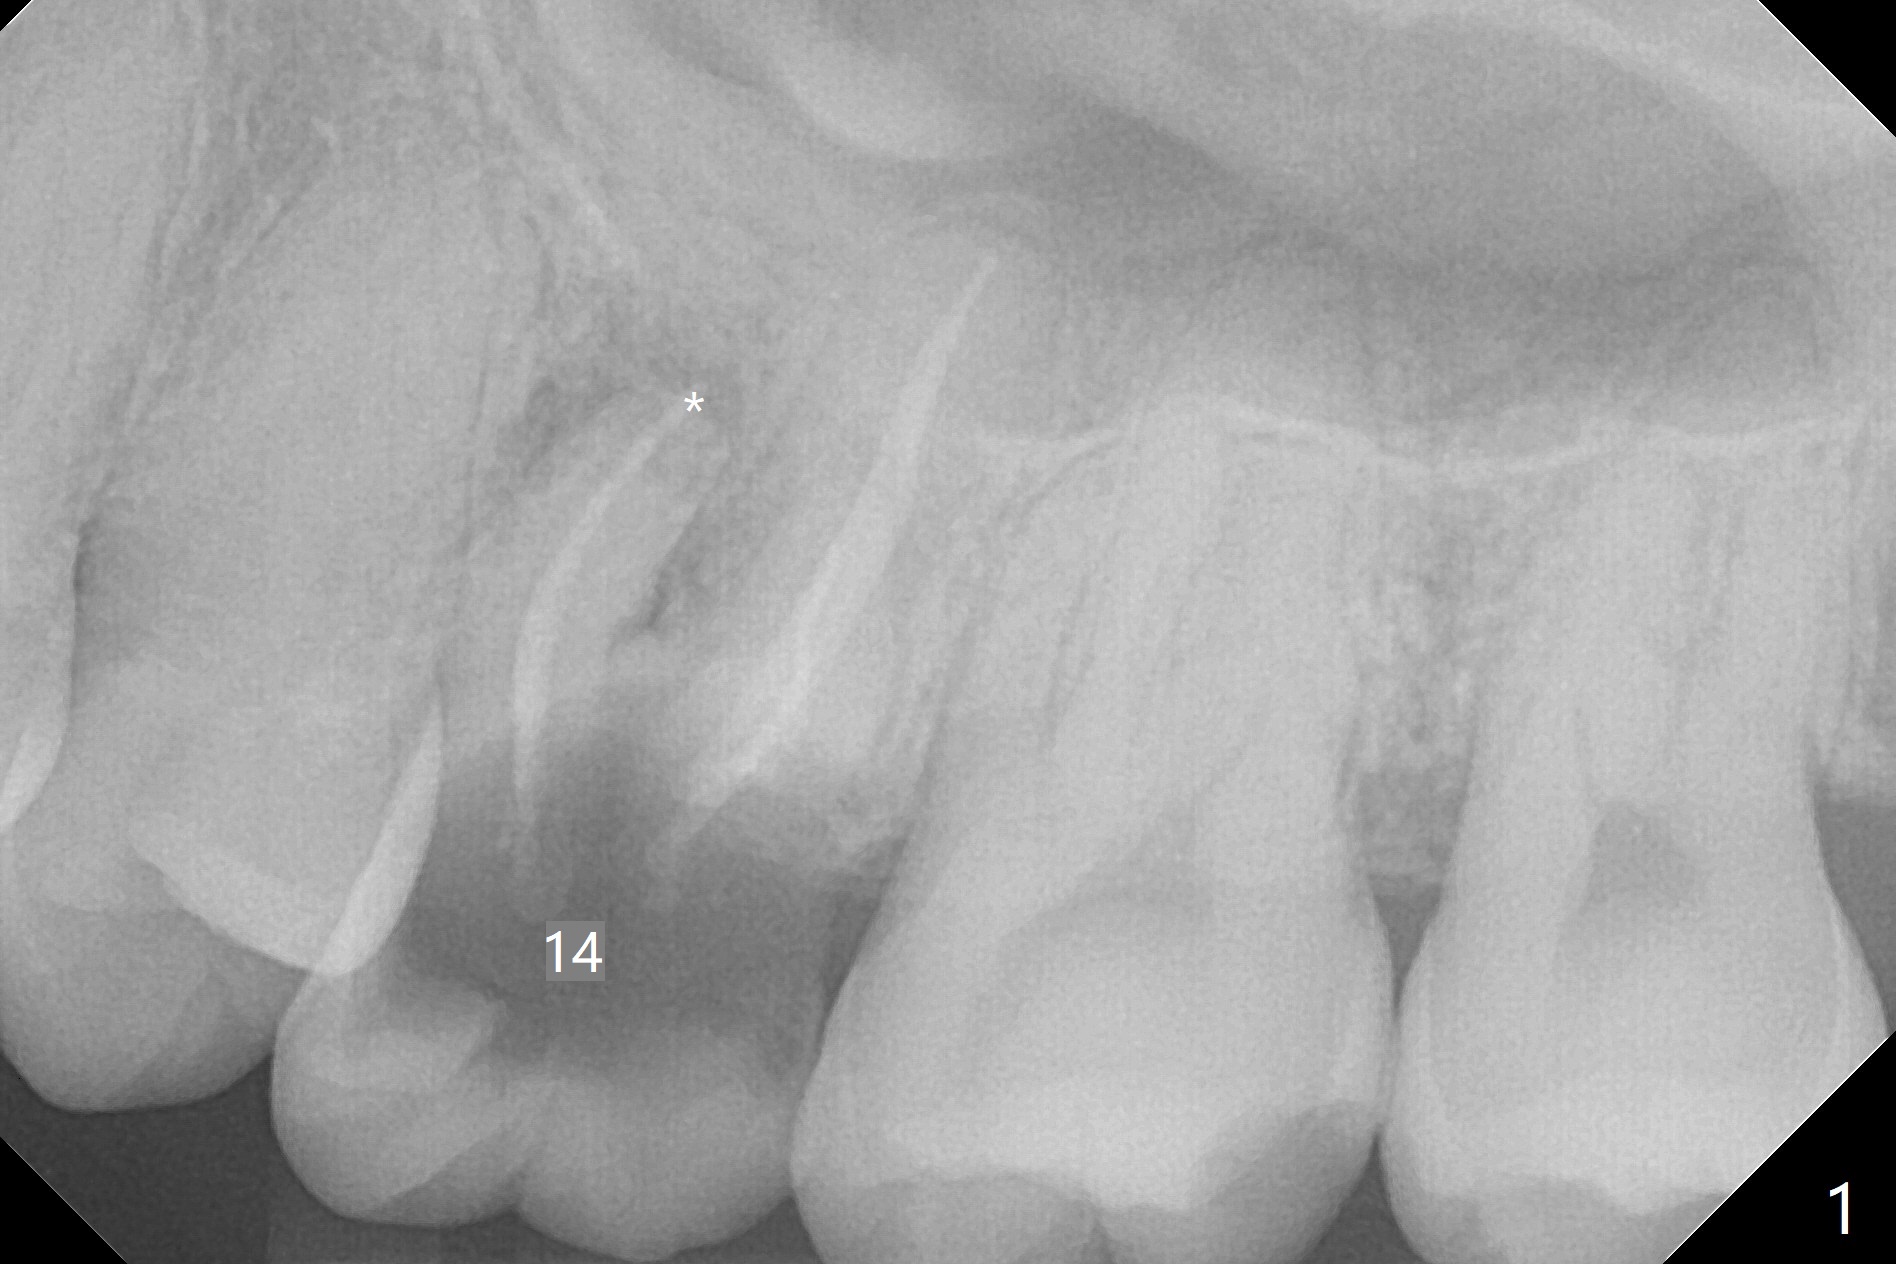

A 38-year-old woman requests extraction of the tooth #14 with mesiobuccal fistula (Fig.1). After extraction, the buccal plate is found to be defective. Bone graft enters the apex of the palatal root (Fig.2 red dashed line) so that the bone height increases by 6 mm (Fig.3). Following placement of collagen plug and suturing, acrylic dressing is applied to the undercuts of the neighboring teeth for retention.